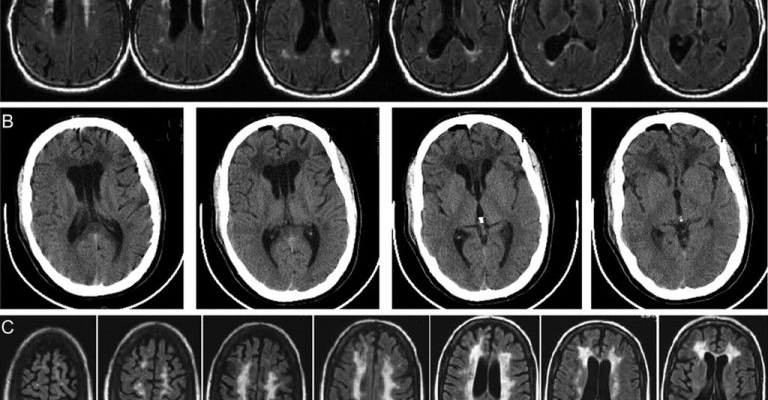

Чтобы обнаружить глиоз, необходимо выполнить магнитно-резонансную томографию, которая не только определяет расположение и размер глиоза, но в некоторых случаях даже предоставляет информацию о возрасте поражения. Это позволяет неврологу в сочетании с другими исследованиями и клиническим обследованием определить, является ли глиоз результатом активного или более раннего изменения ЦНС.

Клинически глиоз может не проявляться, но может быть обнаружен случайно при обследовании по другим показаниям. Помните, что МРТ, показывающая «признаки глиоза», — это не диагноз, а повод пройти комплексное медицинское обследование у специалиста-невролога. Результатом любого такого теста является лечение не глиоза, а заболевания, вызвавшего его.

- Магнитно-резонансная томография (МРТ) — получение изображений внутренних органов и тканей путем воздействия электромагнитных волн на исследуемый объект. Этот метод используется для выявления аномалий органов, новообразований и аномальной регенерации тканей;

- Компьютерная томография (КТ) — визуализация внутренних органов с помощью рентгеновских лучей с последующей обработкой данных на компьютере. Это помогает обнаружить сосудистые изменения, такие как нарушение кровообращения, тромбоз и т. Д .;